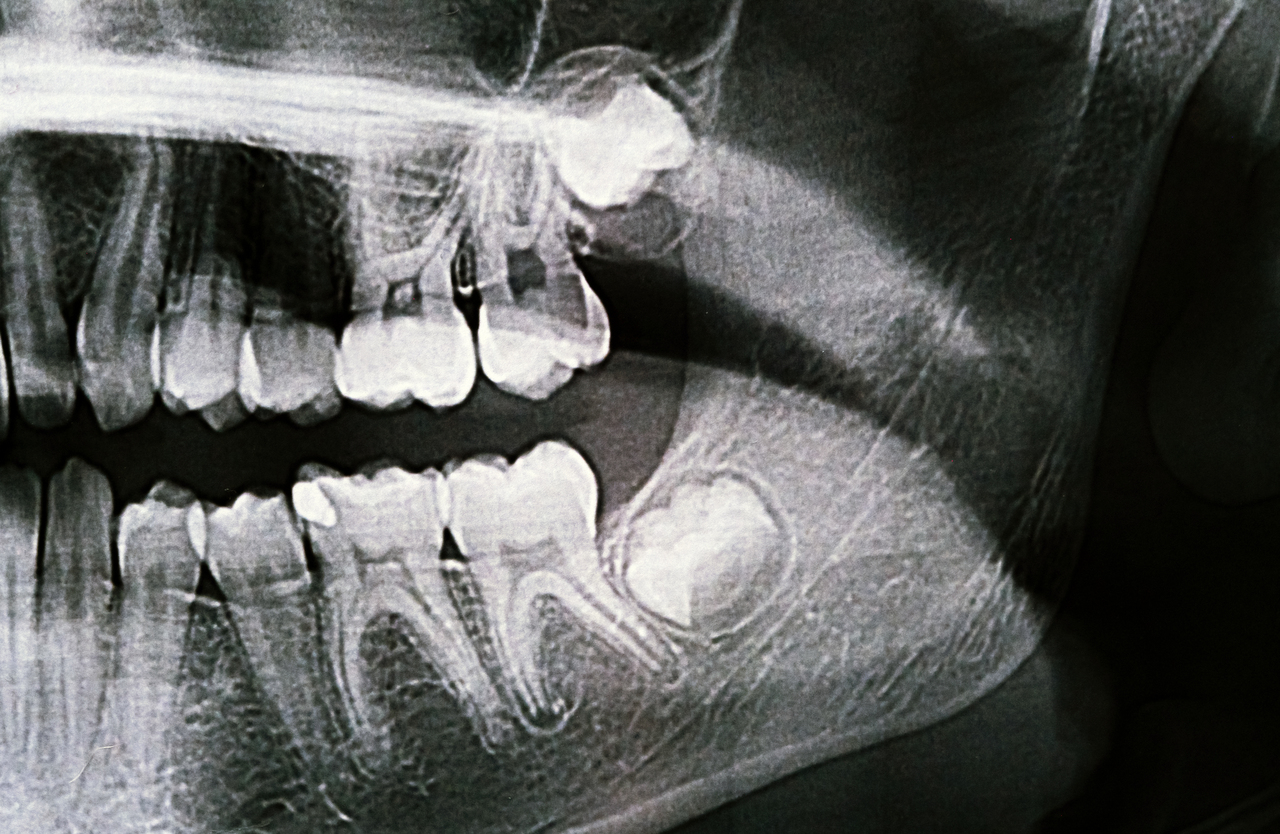

Seorang ortodontis akan menilai gigi dan gigitan anda untuk memutuskan jika braces gigi hanya untuk gigi atas adalah pilihan yang tepat. Doktor gigi kami akan menggunakan alat X-ray untuk mendapatkan gambaran jelas tentang bagaimana gigi dan rahang anda berfungsi bersama.